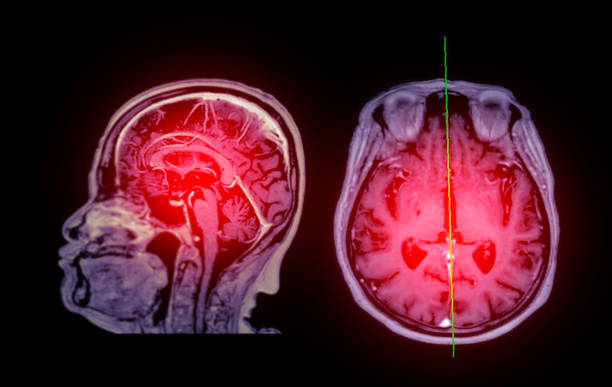

뇌경색 후유증은 심각한 장애를 남길 수 있는 신체적, 정신적 문제를 야기할 수 있는 중요한 주제입니다.

뇌경색 의심이 된다면 빠르게 대응해서 치료를 하는게 좋습니다.

✅뇌경색 후유증 종류

뇌경색 후유증은 다양한 증상을 유발할 수 있습니다. 이러한 증상은 흔히 다음과 같이 나눌 수 있습니다.